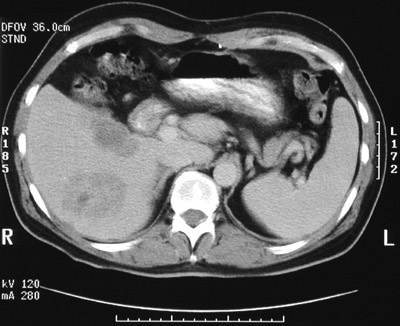

This abdominal CT scan demonstrates multiple subtle hepatic mass lesions in a patient with widespread metastatic carcinoma.